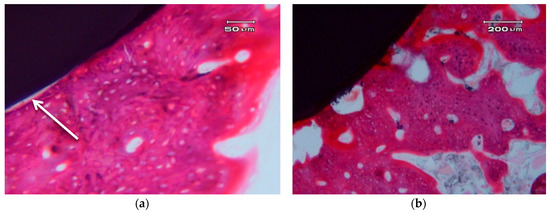

Figure 5 shows the photographs correspond to a transversal cross-section of implant.

Figure 5.

Transversal cross-sections of different nanocomposite ZCe-A implant-bone interfaces after eight weeks of healing. (a,b) show two different interfaces.

In general, we can clearly appreciate bone growth in direct contact with the surface of the implant. There are some areas that present a small gap of less than 5 µm, which can be due to an artefact of the histological process (see arrow in Figure 5a). There is no connective tissue interposed between the surface of the implant and the bone. There are no signs of inflammation at the interface or of adjacent bone. The bone that is in contact with the implant shows, in some areas, very few characteristics of immature bone and a typical woven bone cell distribution (plexiform) (Figure 5b), although it mostly consists of laminar and haversian bone. There are no images of bone sequestration, nor atypia or dysplasia.